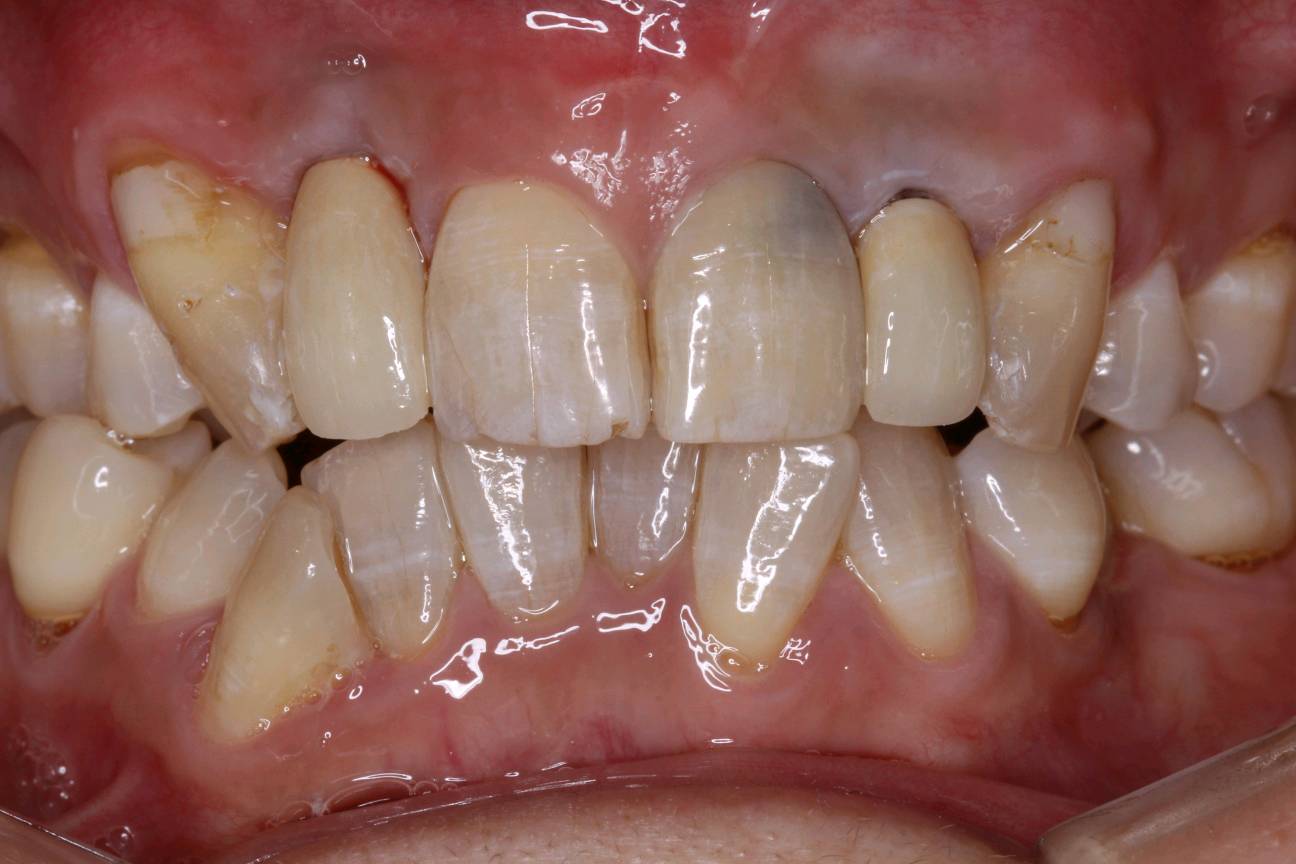

患者要求进行修复,恢复其美观行。而种植牙刚好可以满足患者需求。种植牙还可以获得与天然牙功能、结构以及美观十分相似的修复效果。今日如期佩戴牙齿,患者十分满意,重拾自信微笑。

术后